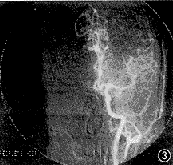

1.螢光血管造影 臂-視網膜循環時間和視網膜循環時間均延長。視盤正常或呈現強螢光。黃斑有點狀螢光素滲漏。後極部和赤道部可見微血管瘤。視網膜動脈、靜脈和小血管、毛細血管均可有螢光素滲漏,靜脈呈串珠狀某些病例可有毛細血管無灌注區和動靜脈交通。